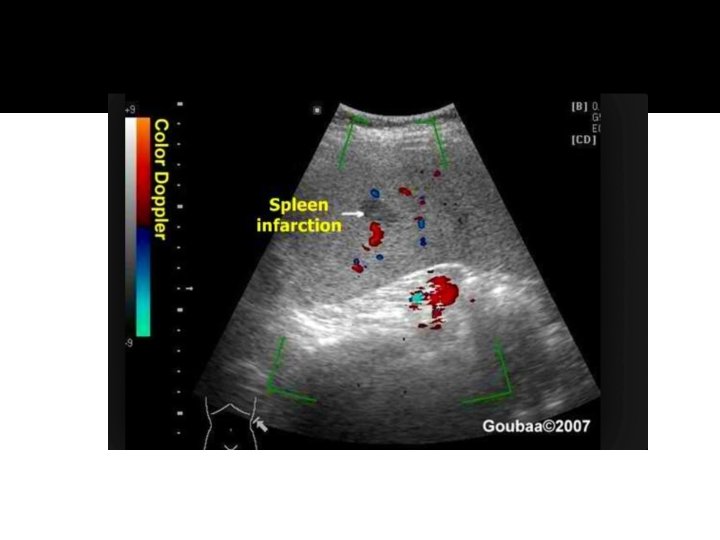

Splenic Infarct �Splenic infarcts are common in patients with bacterial endocarditis and splenic artery aneurysms. �They present as a peripheral wedge-shaped hypoechoic lesion. �The sonographic appearance of an infarct will change over time, as do hematomas. The initial ischemia and edema will appear as a hypoechoic wedge of tissue. With necrosis and liquification, the area will appear anechoic and ultimately will calcify.

Pathology – infarcts- cont… �Sonographically, fresh infarcts are well defined, hypoechoic wedge-shaped focal lesions. The base of the wedge is towards the capsule and the apex towards the hilum. With time, the lesion shrinks and becomes more echogenic. �Complete healing may occur.

Infarct

Splenic Infarct